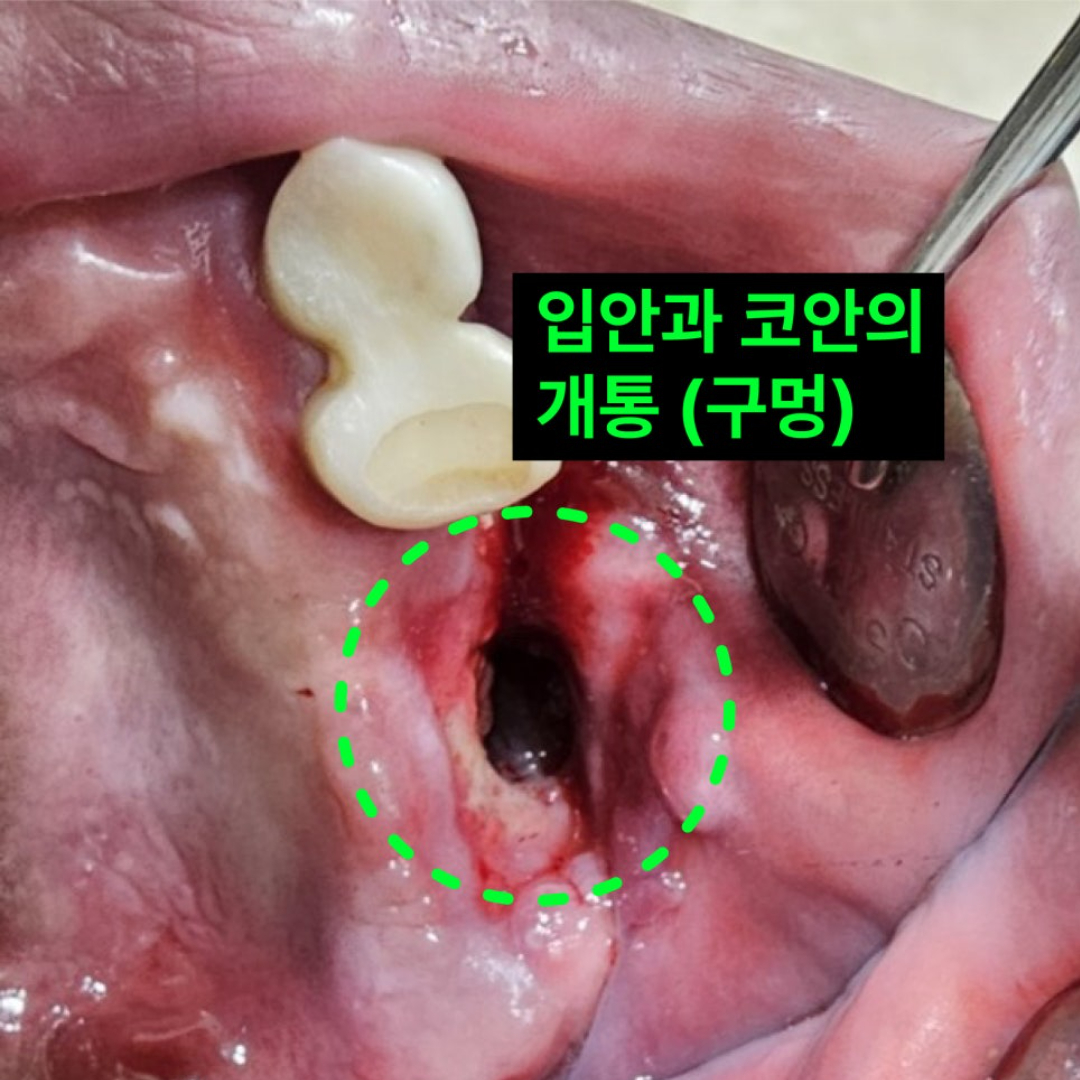

- 상악동 합병증

- 구강상악동 개통(누공) 봉쇄술, 이백점치과의 독보적 해결법

- 상악동 합병증

- 구강상악동 개통(누공) 봉쇄술, 이백점치과의 독보적 해결법